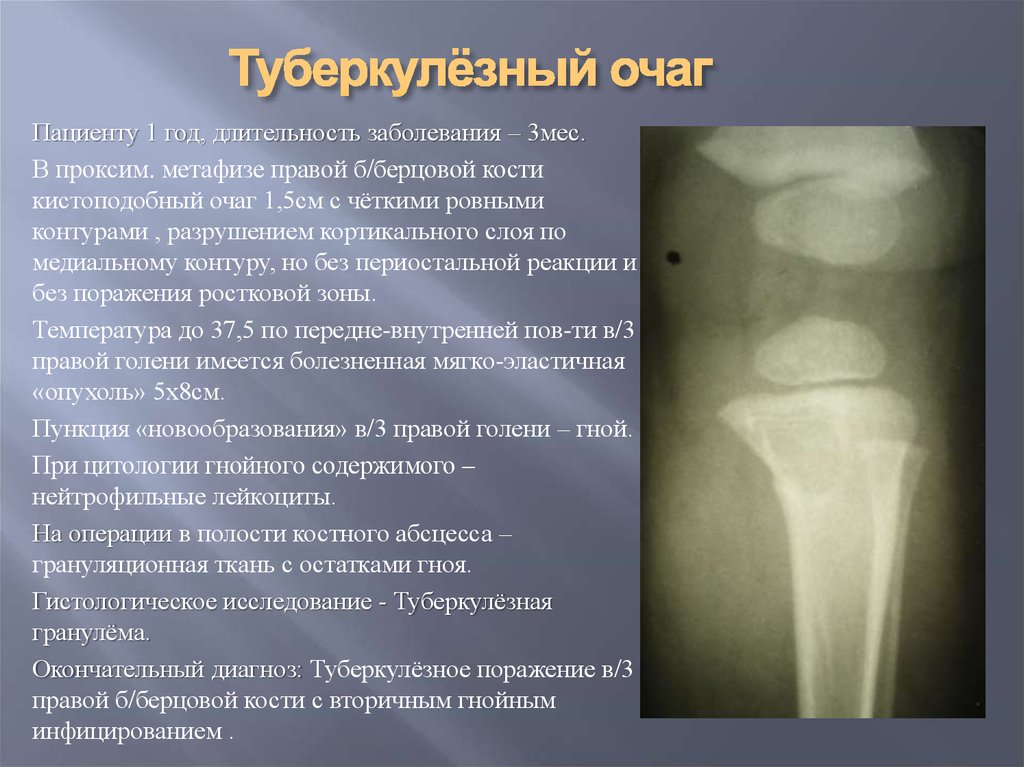

Медицинские аспекты заболеваний: рентгенологическая картина туберкулеза костей

Раздел: Снимки-откровения